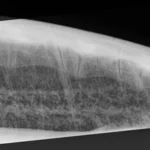

151.9 lbs non -FP green

Tip shaved down, minor abrasions on flippers, minor carapace abrasions

In-house PCV = 30 %, TP = 5.1 g/dl, glucose = 44. Started on Ceftaz, Vitamin B, Normosol w/ Dex